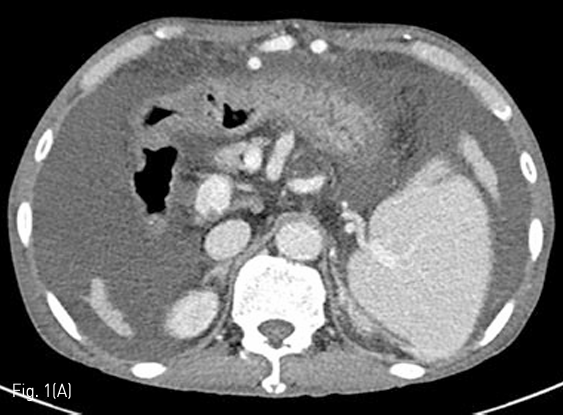

Fluoroscopy 유도하에 경구를 통해 0.035 인치 유도철사 (Glidewire, Terumo, Tokyo, Japan)를 위 속까지 삽입한 후 20mm x 4cm 풍선카테터 (Atlas, BARD, Arizona, USA)를 흉곽입구식도 중간부위에 위치하도록 하였다. 조영제와 생리식염수를 혼합하여 풍선카테터를 팽창시켰고, 초음파 유도하에 팽창된 풍선을 percutaneous transesophageal approach 하여 18게이지 바늘 (Chiba biopsy needle, Cook, Bloomington, USA)로 천자하였다(Fig. 2. A-B). 천자 바늘의 속심을 제거한 후 조영제가 역류되는 것을 확인하였다. J-tip 유도 철사 (J-Tip Glidewire, Terumo, Tokyo, Japan)를 터진 풍선 내로 전진시키고, 터진 풍선과 J-tip 유도철사를 식도하부 혹은 위 안쪽에 위치시킨 후(Fig. 3A) 터진 풍선과 입을 통해 삽입되었던 0.35 인치 유도철사를 제거하고 transesophageal J-tip 유도 철사만 남겨 놓았다. (Fig. 3B) 순차적으로 12Fr, 14Fr dilators (Dilator, Cook, Bloomington, USA)를 이용하여 tract을 확장 시켰다. 18Fr 분리 제거형집(Enteral access dilation system, HALYARD, Alpharetta, USA)을 거치한 뒤 (Fig. 3C) 14Fr 빈천자창냄 카테터(MIC; jejunal feeding tube, HALYARD, Alpharetta, USA)를 십이지장내 세번째 부위까지 진입시키고 분리제거형집을 제거하였다(Fig. 3D). 삽입된 카테터는 목 피부에 봉합하여 고정하고 시술을 종료하였다.

Fig 3B

(B) The tip of the J-tip guidewire is then dislodged from the ruptured balloon and after deflation, the ruptured balloon catheter and 0.035 inch guidewire are removed to leave only the J-tip guidewire.